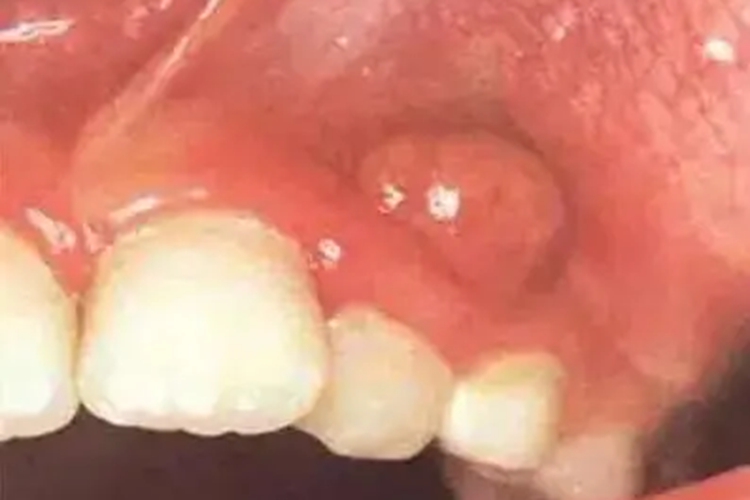

牙龈肿有脓包一直不消可能是由多种口腔疾病引起的,主要包括牙龈炎、牙周炎、根尖周炎等,需要通过药物治疗、根管治疗等方法进行处理。

- 根尖周炎:当龋齿破坏牙髓并扩散到根尖时,可引起根尖周炎,进而在牙龈处形成脓包。

- 脓肿切开引流:当脓液形成并出现波动时,可通过手术治疗切开脓肿,并进行引流。切开后用生理盐水、过氧化氢溶液等冲洗脓腔,促进脓液排出和炎症消散。如果存在大量牙结石,还需通过超声波洗牙去除。